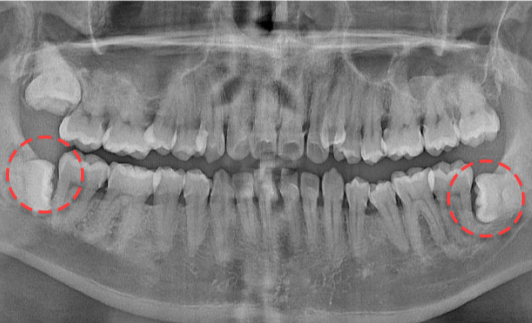

• BEFORE

양쪽 하악 매복 사랑니 발치 Before X-Ray

치료시작일

2019.11.05

AFTER

양쪽 하악 매복 사랑니 발치 After X-Ray

치료종료일

2020.12.24

양쪽 하악 매복 사랑니 발치